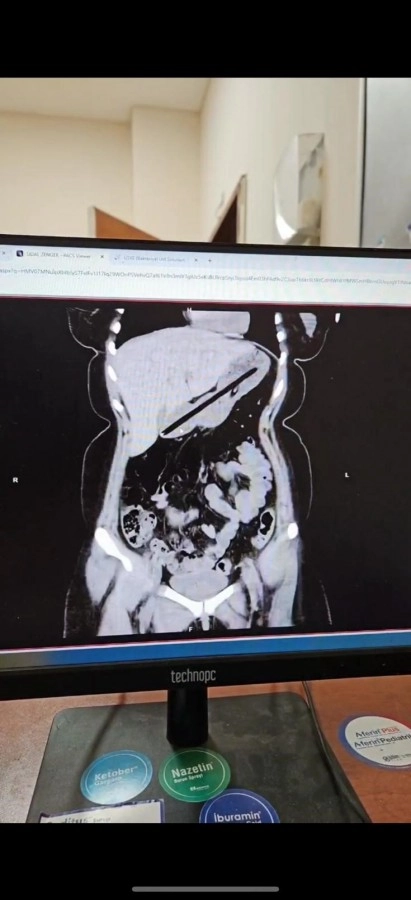

Ağrı'da Obsesif KompulsifBozukluk (OKB) rahatsızlığı bulunan 22 yaşındaki kadın, kalem yutma şikayetiyle hastaneye kaldırıldı. Ailesi tarafından Ağrı Eğitim ve Araştırma Hastanesi Acil Servisi'ne getirilen hastanın midesinde yabancı cisim tespit edildi. Genel Cerrahi ekibince ertesi gün gerçekleştirilen yaklaşık bir buçuk saat süren endoskopi operasyonuyla genç kadının midesinden biri kurşun, diğeri tükenmez olmak üzere iki kalem çıkarıldı. Başarıyla sonuçlanan operasyonun ardından hasta bir gün müşahede altında tutularak taburcu edildi.

Operasyonu gerçekleştiren Dr. Öğretim Üyesi Adem Aslan, ilk kez böyle bir vakayla karşılaştıklarını belirterek, "22 yaşındaki bayan hastamız kalem yutma şikayetiyle ilçe devlet hastanemize başvurmuştu. Tomografisinde midesinde yabancı cisim olduğu görüldü. Biz de tetkiklerimizde midesinde kalem olduğunu gözlemledik. Daha önce toplu iğne, kemik parçası gibi yabancı cisimlerle karşılaşıyorduk ama bu kadar uzun ve ince bir cisim ilk kez karşımıza çıktı. Midenin boşalması için bir gün bekledik ve ertesi gün yaptığımız endoskopide hastanın bir değil iki kalem yuttuğunu gördük. Yaklaşık bir buçuk saat süren işlemde kalemleri endoskopik yöntemle çıkardık. Hastamızın Obsesif Kompulsif Bozukluğu olduğu için ailesine yalnız bırakmamalarını ve bu tür cisimleri ortalıkta bulundurmamalarını tembih ettik. Bir gün müşahede altında tuttuktan sonra şifa ile taburcu ettik" dedi.